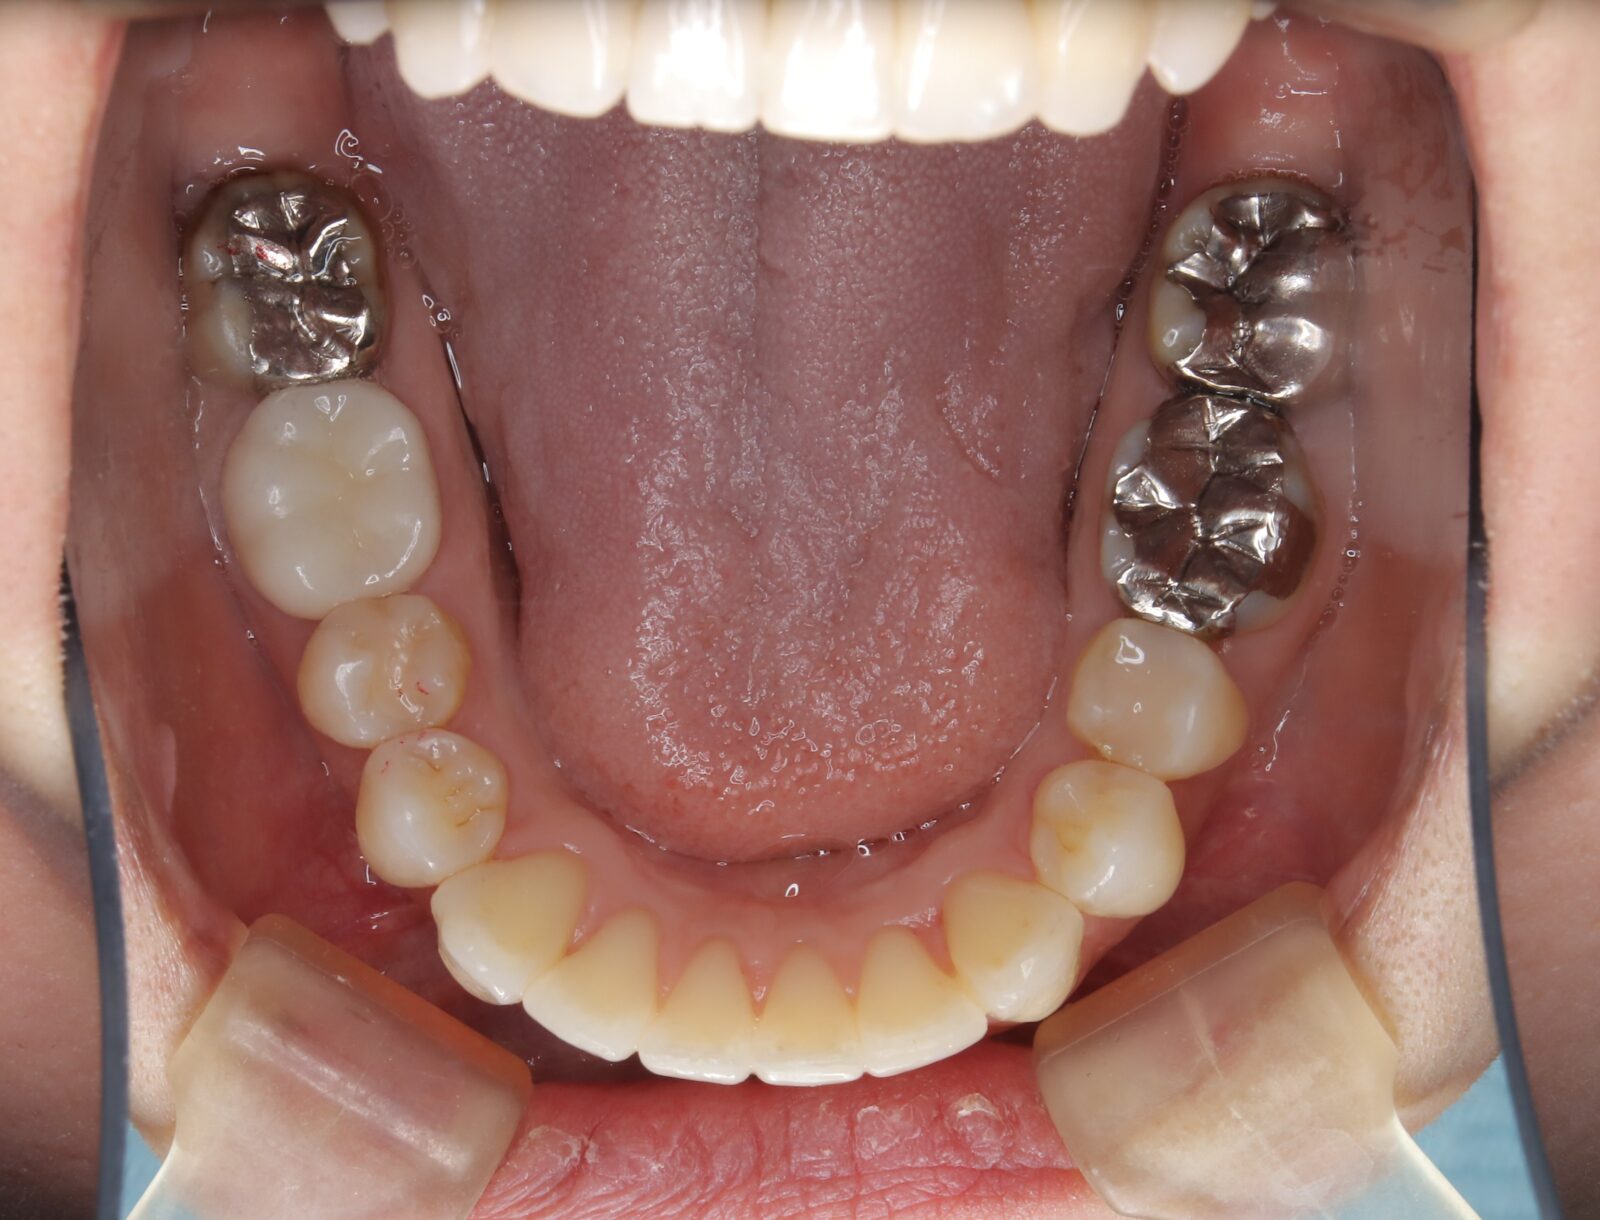

インビザライン(全体矯正)+ホワイトニングコースの症例

上下の前歯の歪みと奥歯のすれ違いをインビザライン(全体矯正)とホワイトニングで綺麗に矯正。

・費用:935,000円(税込)

・治療期間:30ヶ月

・通院回数:30回

・31歳女性